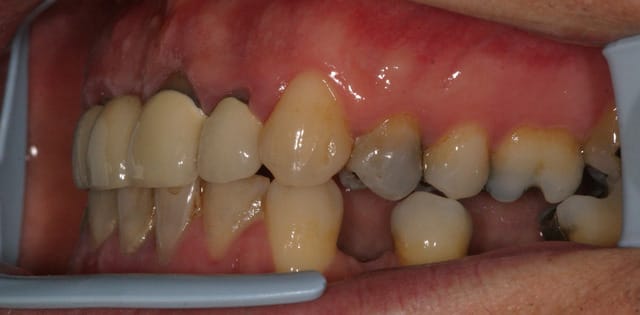

tient un boulot ou il y a un peu de tout.

bridge antérieur , car la pose d'implants nécessitait de la reconstruction trop importante, endo couronne sur les molaires mandibulaires par manque de hauteur, onlay. implants à la mandibule.

A noter les 2 PM maxillaires qui comportaient

chacune 3 canaux.